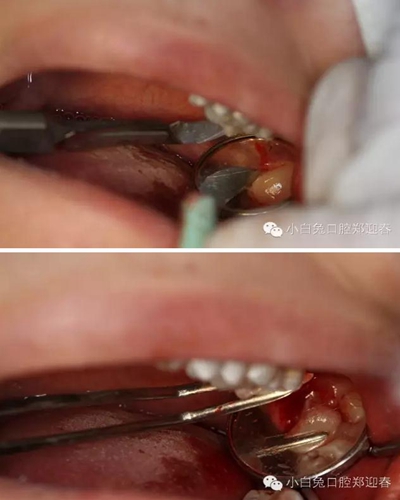

利用微創(chuàng)拔牙標(biāo)準(zhǔn)進(jìn)行阻力冠切割

切割過(guò)程對(duì)冷卻和角度的要求,一定要是水柱的噴射。

渦輪動(dòng)力切割阻力牙冠

“T”型分割近中阻力冠

分別去除近中阻力冠的頰和舌部的牙冠

微創(chuàng)牙挺挺出28

創(chuàng)口置入膠原蛋白明膠

拔除術(shù)的離體28、38